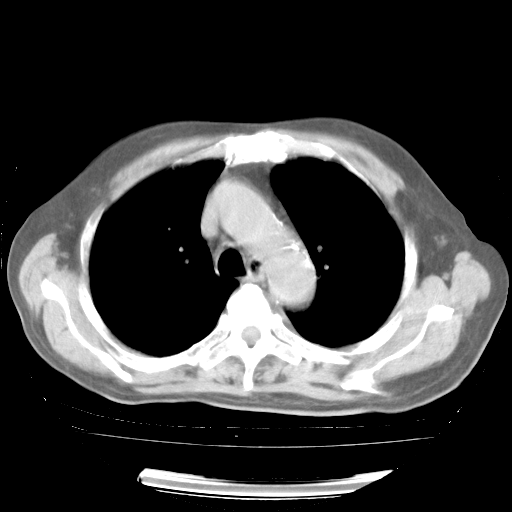

4月28日肺部CT——再次出现类似去年5月9日——透光度降低,“间质性”改变。

4月28日肺部CT——再次出现类似去年5月9日——磨玻璃样、间有“粟粒样”改变。

4月28日肺部CT